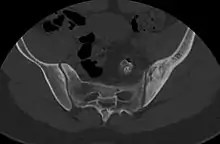

CT scan of primary B cell lymphoma in the left ilium, as diffuse cortical and trabecular thickening of the hemipelvis, mimicking Paget's disease.[6]